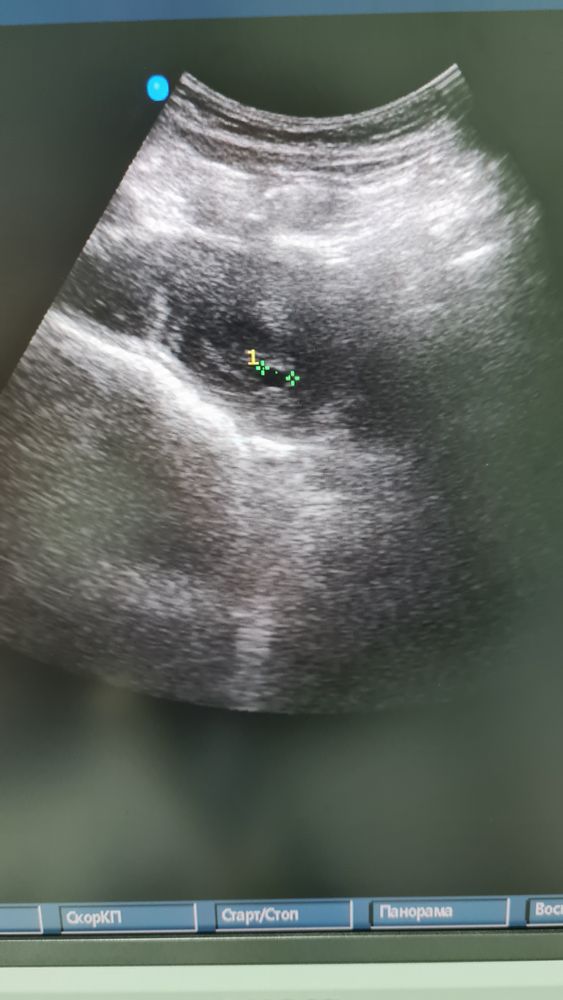

Беременность 5недель, скажите пожалуйста , на узи 1 плодное яйцо или 2?

Одно